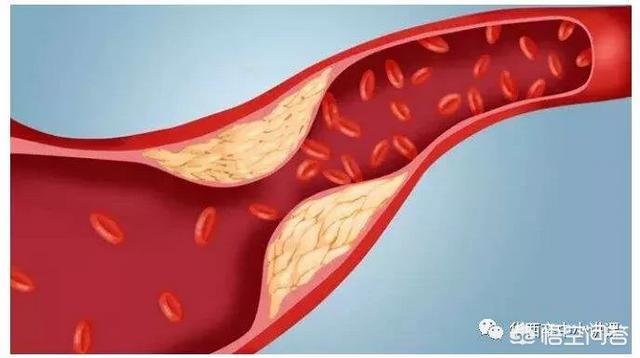

Sous l'influence de facteurs de risque cardiovasculaire tels que l'hyperlipidémie, la paroi interne des vaisseaux sanguins est progressivement endommagée et les lipides en excès dans le sang se déposent progressivement sous la paroi du vaisseau, formant un noyau lipidique athéromateux jaune, et finalement une chape fibreuse se forme dans le noyau lipidique, ce qui constitue le processus de formation de la plaque artérielle. La plaque est un facteur de risque conduisant à l'athérosclérose, et les plaques qui ont des problèmes de stabilité et se rompent peuvent conduire à une agrégation plaquettaire réactive. L'agrégation réactive des plaquettes peut même conduire à la formation de caillots sanguins, bloquant les vaisseaux artériels et provoquant des maladies cardiovasculaires infarciques. Ce qu'il faut faire, c'est prévenir la formation de la plaque par des médicaments et des exercices raisonnables, essayer de maintenir la stabilité de la plaque existante, ralentir le processus d'athérosclérose et empêcher la rupture de la plaque d'entraîner un risque plus élevé.

La plaque a la plaque veineuse, la plaque artérielle, c'est dans le rôle de multiples facteurs étiologiques, en raison de la lipidation de la précipitation, pour dire les choses franchement, c'est-à-dire, vous graissez plus, la digestion et l'utilisation ne peut pas être, dans les lipides sanguins quatre et d'autres facteurs multiples sous l'influence de et puis des dommages à l'intima, le dépôt à la couche interne des vaisseaux sanguins, la formation d'un noyau lipidique jaune athéromateux, et finalement dans la formation d'un noyau fibreux sur le noyau lipidique, qui est normalement très stable, si la coiffe fibreuse est soumise à une inflammation soutenue. la chape fibreuse se rompt, la plaque s'écoule et les plaquettes sanguines dans le mariage éclair donnent naissance à un enfant perturbateur, appelé thrombus, qui se promène pour semer le trouble, se spécialise dans les mauvaises actions pour bloquer les vaisseaux sanguins, le thrombus dans la lumière des vaisseaux sanguins devient plus étroit en même temps, mais aussi se rompt, déclenchant des événements vasculaires cardio-cérébraux et cérébraux aigus, tels que l'accident vasculaire cérébral, l'infarctus du myocarde, l'embolie pulmonaire, l'insuffisance rénale, les veines variqueuses, etc. etc. Par conséquent, l'élimination de la plaque ne permet pas seulement de déboucher les vaisseaux sanguins, mais aussi de prévenir les accidents cardiovasculaires et cérébrovasculaires aigus, ce qui est dans l'esprit de tout le monde.

La plaque artérielle est une série de réactions inflammatoires déclenchées par des lésions de la paroi artérielle sous l'effet de multiples facteurs étiologiques, avec la formation ultérieure d'une plaque athéromateuse secondaire. La formation de la plaque est plus nocive pour le corps humain, elle rétrécit la lumière du vaisseau sanguin en même temps, elle peut aussi se rompre, déclenchant des événements cardiovasculaires aigus, par conséquent, l'élimination de la plaque non seulement débouche le vaisseau sanguin, mais prévient également les événements cardiovasculaires aigus, qui sont le battement de cœur de tous les patients. Pour le traitement de la plaque, nous pouvons commencer par la cause de la maladie, comme le contrôle des lipides sanguins, de la tension artérielle, de la glycémie, etc., ainsi que le changement d'un mauvais mode de vie, comme un régime pauvre en sel et en cholestérol, l'augmentation de l'exercice, l'arrêt du tabac et la limitation de l'alcool, etc. ou, en plus du traitement ci-dessus, nous pouvons donner des médicaments, et le choix du médicament est la statine, comme l'atorvastatine, la reserpulvastatine et ainsi de suite sont couramment utilisés dans le traitement des plaques d'athérome, et le choix exact du traitement doit être formulé sous la direction d'un médecin spécialiste. Le choix exact du traitement doit être formulé sous la direction d'un médecin spécialiste. Le plan de traitement spécifique doit être formulé sous la direction de médecins spécialistes.

Cependant, même lorsque ces traitements sont administrés, la plaque artérielle est difficile à éliminer. De nombreux patients ont entendu dire que les statines pouvaient inverser la plaque, mais par inverser la plaque, nous entendons transloquer les lipides hors de la plaque, réduire la plaque d'athérome, augmenter sa stabilité, réduire le risque de rupture et diminuer le risque d'événements cardiovasculaires, et non pas éliminer complètement la plaque du vaisseau sanguin, pour ainsi dire, et une fois que la plaque est formée, il est presque impossible de l'enlever.

Le processus de formation de la plaque passe par plusieurs étapes : tout d'abord, l'endothélium du vaisseau sanguin est endommagé, comme si la couche protectrice de la surface interne du vaisseau sanguin était "brisée" ; les macromolécules de graisses présentes dans le sang sont transportées par une sorte de substance appelée lipoprotéine de basse densité dans la couche intima-média de la paroi du vaisseau sanguin, où elles s'accumulent en grandes quantités ; la paroi du vaisseau sanguin s'épaissit et le traitement médical consiste à épaissir la couche intima-média de plus d'un millimètre, ce qui est considéré comme de l'athérosclérose. Lorsque l'épaississement de la couche intima-média dépasse 1 mm, on parle d'athérosclérose, telle que l'agrégation locale en une masse, c'est-à-dire la plaque précoce.

Au début de la formation de la plaque, l'accumulation de graisse provoque une série de réactions inflammatoires ; en fait, la graisse est constamment oxydée, dénaturée et forme des substances ressemblant à de la bouillie ; ces substances détruisent la structure normale des vaisseaux sanguins et deviennent partie intégrante des vaisseaux sanguins ; à ce moment-là, la matière lipidique est principalement à l'état liquide, ce que l'on appelle généralement des taches molles.